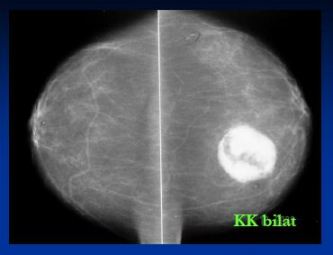

- Klientka odeslána do FN HK s Hi (CCB) ověřenými mikrokalcifikacemi na rozhr.ZQ sin

- Pouze v MDL projekci zachyceno 4mm ložisko v HQ – popsáno jako intramam.LU, nemá korelát v KK

- Ve FN HK před výkonem před lokalizací vodičem zhotoveny KK a bočná projekce sin

- Ložisko v KK projekci (CCB Hi: duktální Ca)